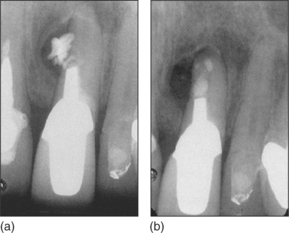

Closure of lateral perforation

An iatrogenic defect in the surface of the root due to instrumentation can result in local infection and inflammation, similar to a failure of apical sealing. Provided that access is adequate, such perforations may be sealed by techniques similar to retrograde root filling (Fig. 6.16). If the perforation is directly on the mesial or distal aspect of the root, and particularly if the perforation is large or the roots are close together, access is often so poor that a satisfactory result cannot be achieved. However, such defects can sometimes be managed by conventional endodontics.

image

Fig. 6.16 (a) A perforation has occurred at the side of the root during preparation for a post and material has been extruded into the periodontal ligament. (b) Following sealing of the perforation and the apex with IRM® there has been bony repair.